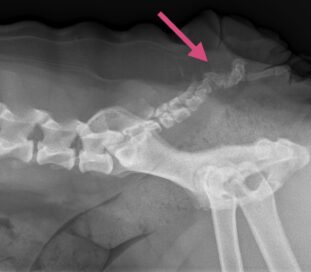

Før operationen tages et røntgenbillede af bagparten, så halehvirvlernes placering kan vurderes.

Der lægges et ovalt snit rundt omkring halens tilhæftning på rumpen. Ud fra røntgenbillederne vurderes halehvirvlernes udformning og ud fra dette besluttes, hvor snittet skal lægges. Det er stort set aldrig muligt at bevare noget af halen.

Huden sys sammen, og der tages et nyt røntgenbillede af halen.